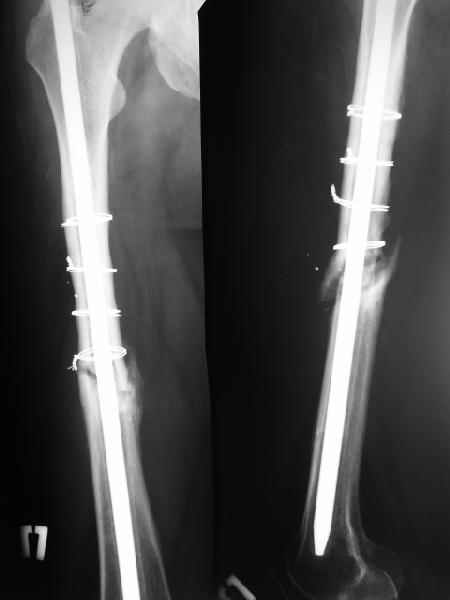

На данный момент правая голень срослась, больной активен в пределах постели. Второе(правое) бедро стабилизированное (рис. до и после). движения в коленном суставе: сгибательная контрактура правого коленного сустава 90, левого 145.

Наверное, мы привыкли, что штифт должен сидеть в костномозговом канале плотно. Гвоздь же этот, сидит относительно свободно, и это нас настораживает, не будет ли микроподвижность которая приведет к рецидиву ложного сустава.